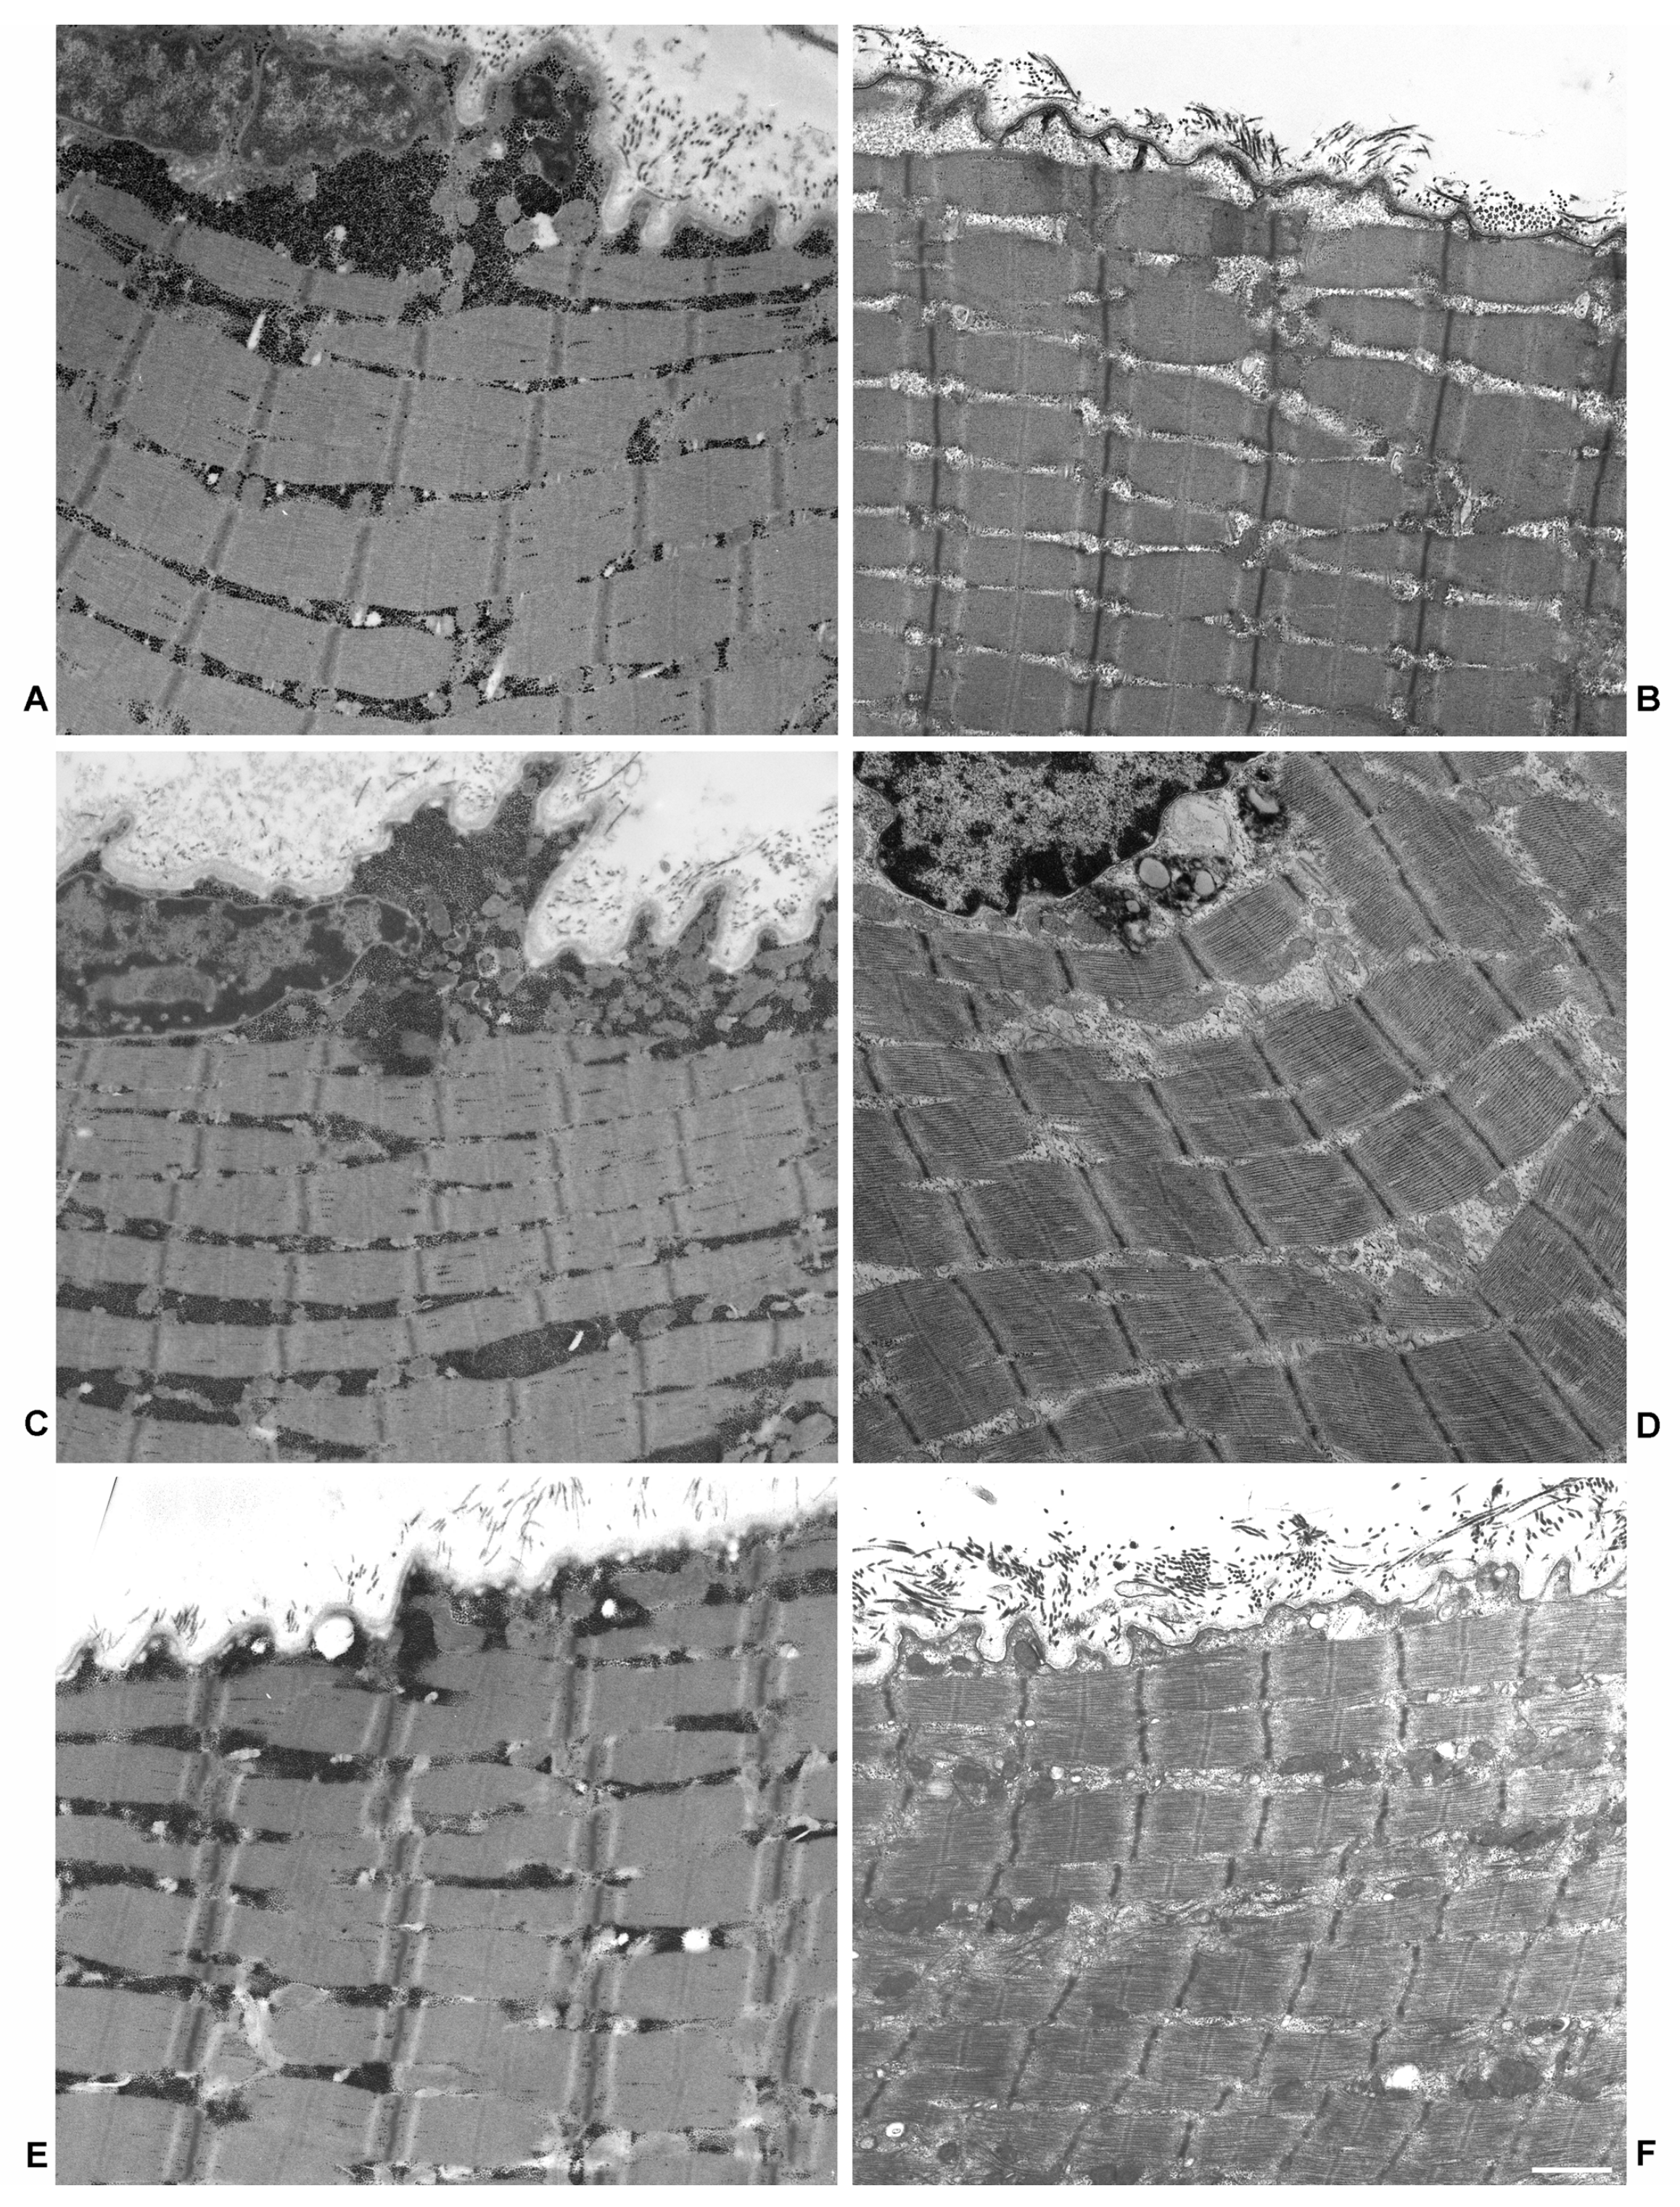

2.1. Electron Microscopy

4.3. Electron Microscopy